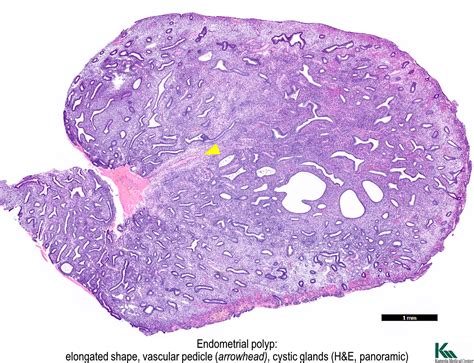

• Endometrial Biopsy: A small sample of the endometrium is taken for laboratory analysis to evaluate its structure and function.